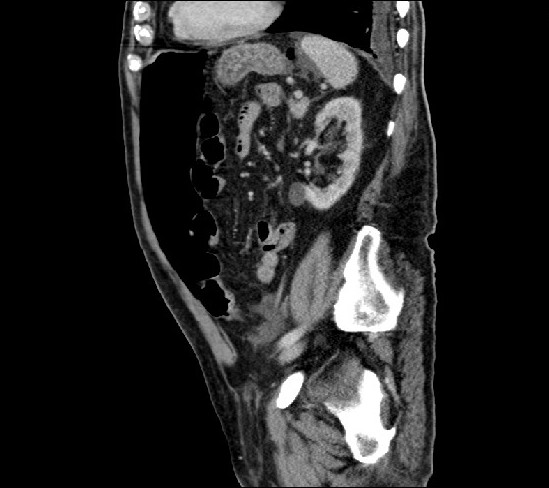

Image of the month